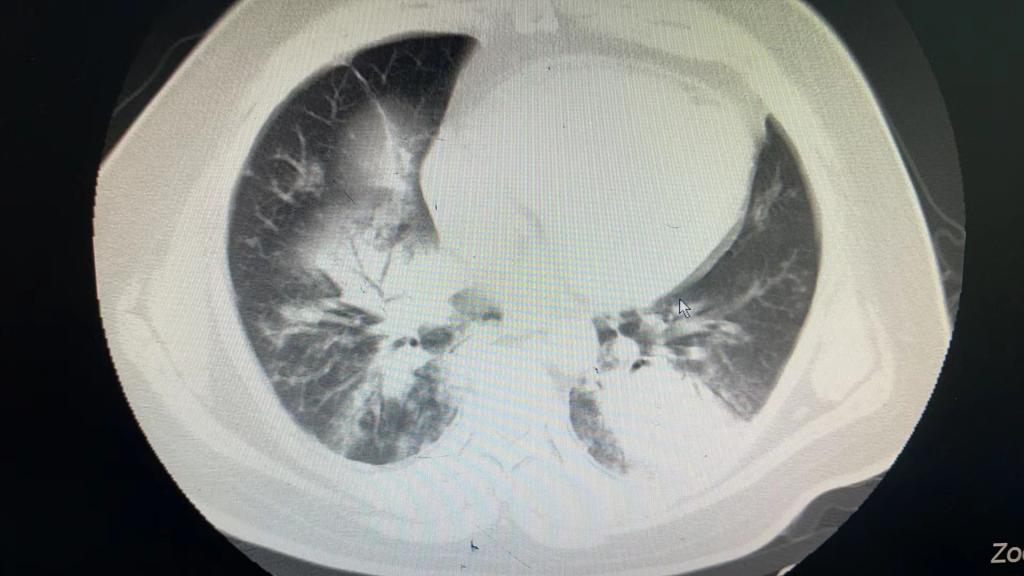

患者以“发热6天伴呼吸衰竭”从外院转入我院EICU,CT呈“白肺”样改变,入院后气管插管呼吸机辅助通气,氧浓度100%,血氧饱和度不到80%,氧合指数只有50,生命岌岌可危。千钧一发之际,ECMO团队迅速全面的病情评估后,紧急启用ECMO支持治疗。

图1 图2腺病毒感染的白肺